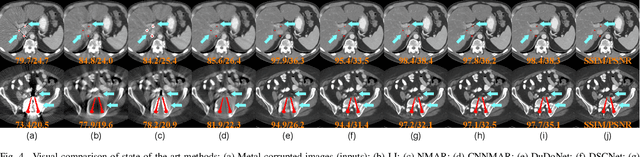

Abstract:The presence of high-density objects such as metal implants and dental fillings can introduce severely streak-like artifacts in computed tomography (CT) images, greatly limiting subsequent diagnosis. Although various deep neural networks-based methods have been proposed for metal artifact reduction (MAR), they usually suffer from poor performance due to limited exploitation of global context in the sinogram domain, secondary artifacts introduced in the image domain, and the requirement of precise metal masks. To address these issues, this paper explores fast Fourier convolution for MAR in both sinogram and image domains, and proposes a Fourier dual-domain network for MAR, termed FD-MAR. Specifically, we first propose a Fourier sinogram restoration network, which can leverage sinogram-wide receptive context to fill in the metal-corrupted region from uncorrupted region and, hence, is robust to the metal trace. Second, we propose a Fourier refinement network in the image domain, which can refine the reconstructed images in a local-to-global manner by exploring image-wide context information. As a result, the proposed FD-MAR can explore the sinogram- and image-wide receptive fields for MAR. By optimizing FD-MAR with a composite loss function, extensive experimental results demonstrate the superiority of the proposed FD-MAR over the state-of-the-art MAR methods in terms of quantitative metrics and visual comparison. Notably, FD-MAR does not require precise metal masks, which is of great importance in clinical routine.